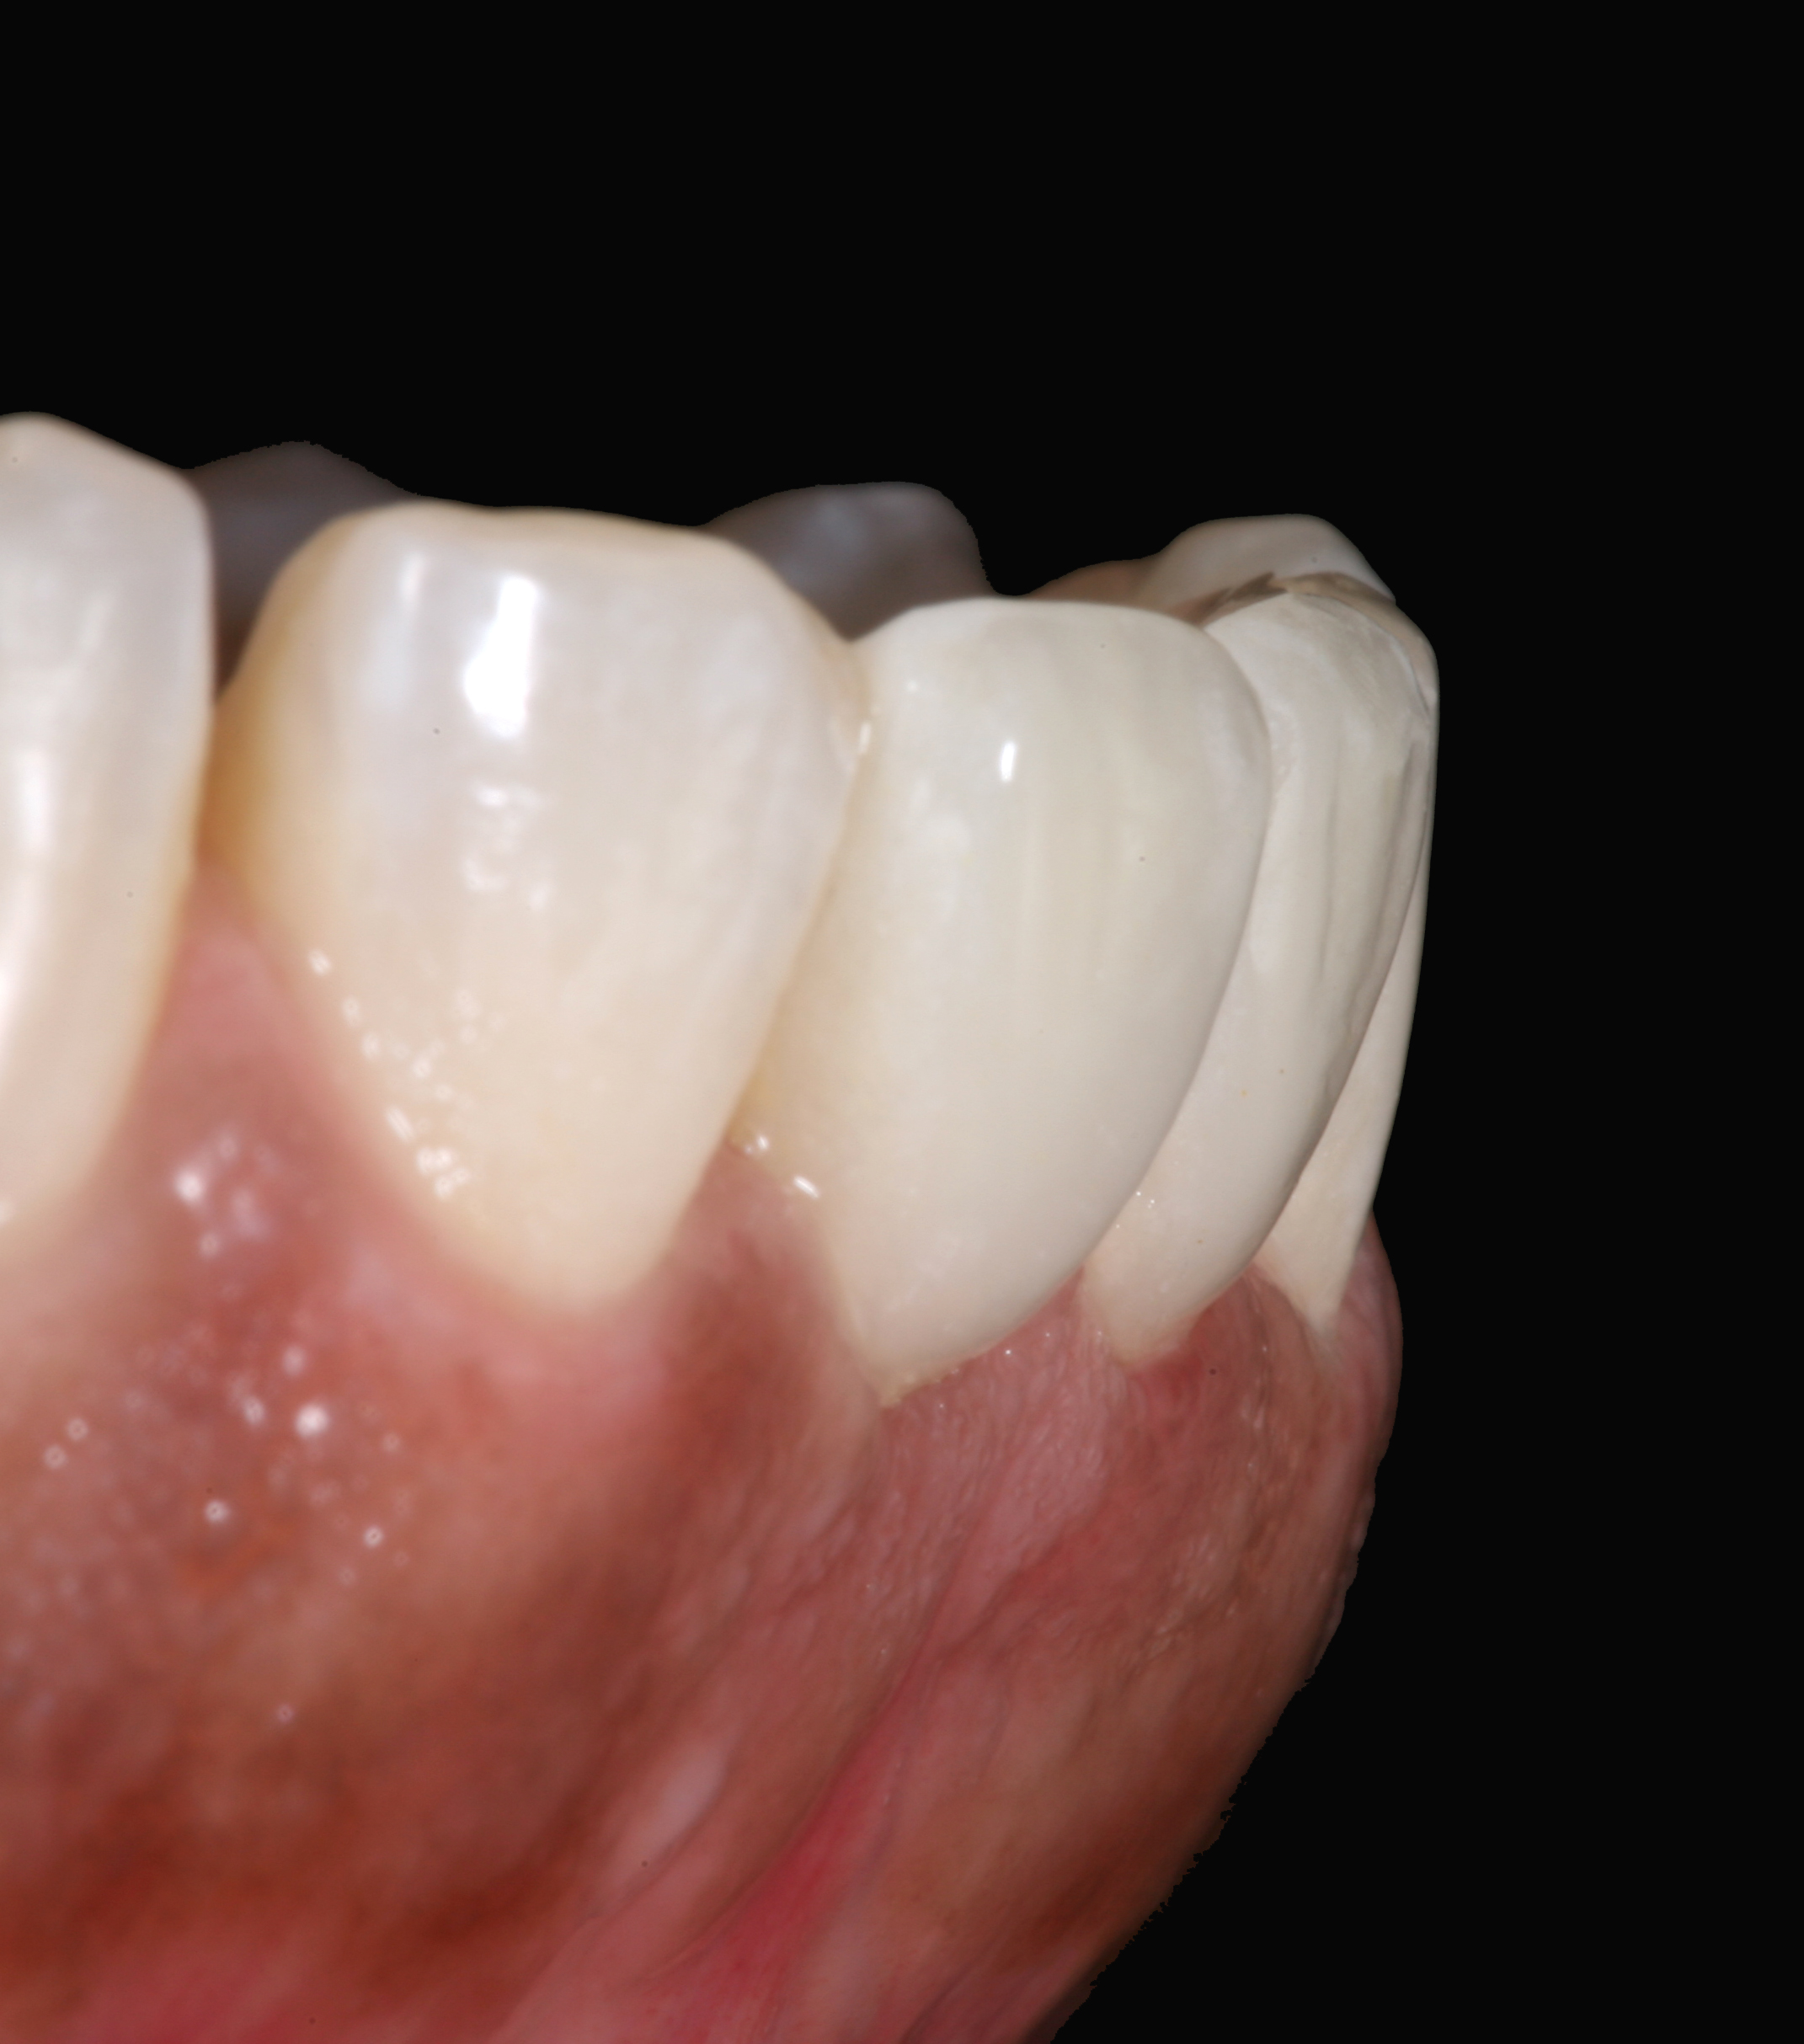

Postoperative situation: left lateral view.

Figure 11

Postoperative situation: right lateral view.

Figure 12

High-strength ceramic materials can be used in select cases to fabricate resin-bonded bridges to replace missing teeth as an alternative to removable prostheses or more invasive procedures such as conventional bridges or dental implants. The two missing lower central incisors (Figure 6) were replaced with two zirconia-based resin-bonded bridges (Figure 7). The single-retainer wing design has shown more than 94% clinical success after 10 years, which is significantly higher than the conventional two-retainer design (67.3% success).6 Proper bonding, however, is key for success and employs an air-particle abrasion step (Figure 8) followed by the application of a special ceramic primer (Figure 9). Figure 10 through Figure 12 demonstrate the clinical outcome.